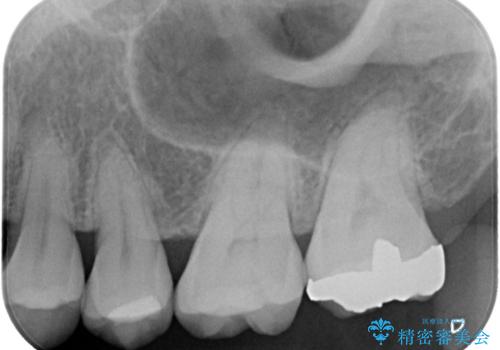

- 主訴:左上の銀の詰め物、笑うと見えそうで気になるので白くしたい。

保険適応のメタルインレーが入っていたため、適合性・審美性の良いセラミックインレーでのやり替えとなりました。

保険適用のメタルインレーを除去したところ、歯質との境目部分にカリエスを認めたため、カリエス除去しCR裏層の後、セラミックインレーを形成しました。